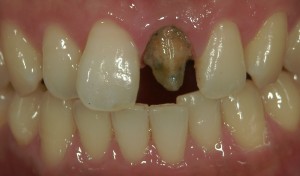

術後

かぶせものをとると中はこのように傷んでいることが多く、この方の場合も歯根がかなり傷んでしまっていることがわかります。

それは新しくつくるセラミックスでも同様です。歯の形がぼてっとしていたり段差があったり、からだと調和しないものであればトラブルが起こりやすくなってしまいます。